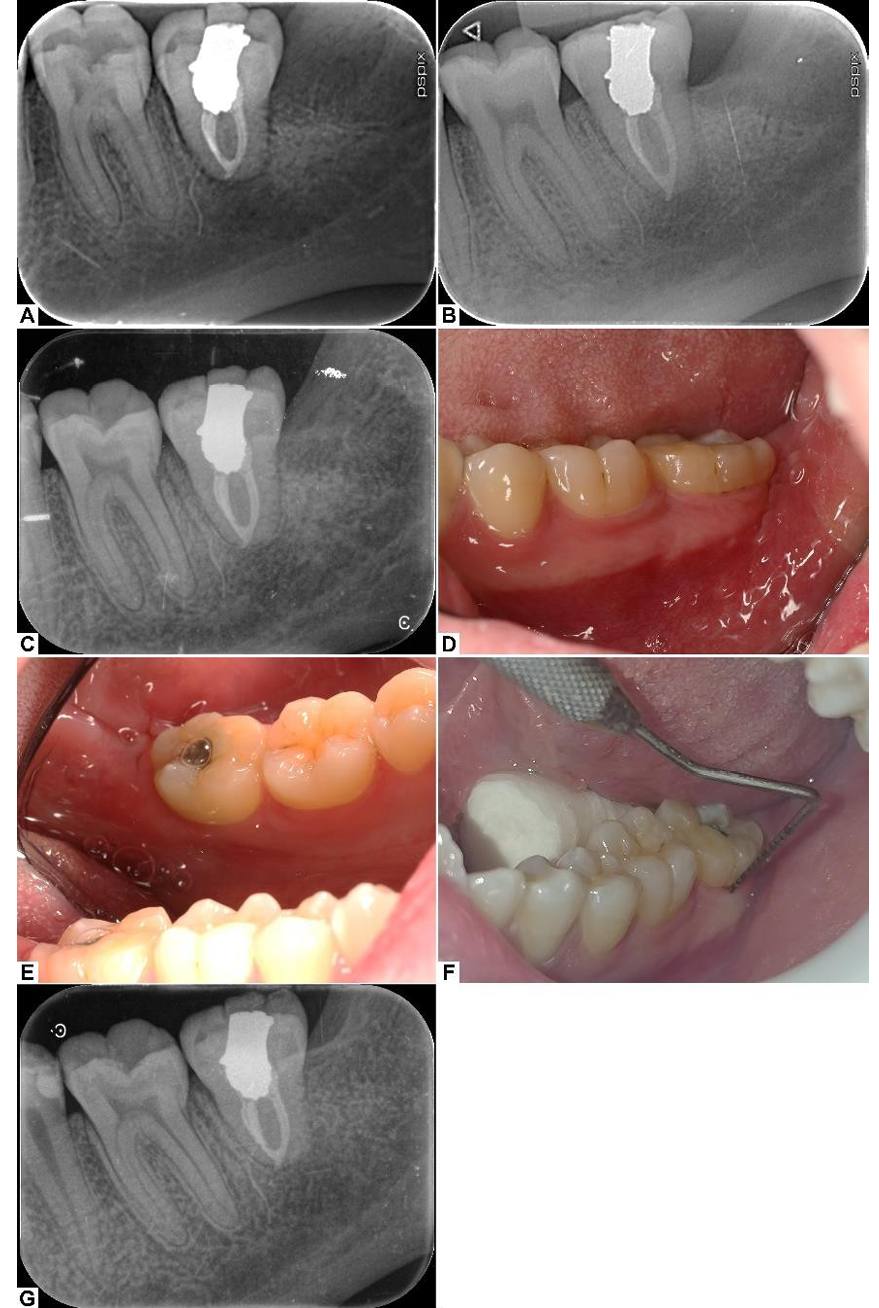

The patient returned for suture removal on the 12th day after the surgery. Healing was uneventful, and the patient was asymptomatic. The periapical radiograph revealed early signs of periradicular healing, especially in the apical region (Figure-4.A).

At the 3-months post-op follow-up visit, the patient was asymptomatic, had no complaints, and the tooth was functioning normally. The periapical radiograph revealed noticeable healing and maturation of periradicular tissues, with a distinct PDL space and early formation of lamina dura (Figure-4.B).

The next follow-up visits were held 6 and 12 months after the surgery. Clinical examination yielded nothing of significance; the gingiva was healthy and free of inflammation, probing depth was within normal limits (Figure-4D and 4E and 4F), the tooth was not tender to percussion or palpation, and it had normal mobility according to the Miller classification [13]. On radiographic examination, a fully formed lamina dura and a distinctive PDL space could be observed. No pathologic periapical radiolucency was observed, and the peri-radicular and crestal bones were normal (Figure-4C). The 1-year post-op periapical radiograph showed proper healing and no signs of negative outcomes such as external root resorption (Figure-4-G).

Figure 4. Periapical radiographs at 2 weeks (A), 3 months (B), 6 months (C) post-op; progressive healing and maturation of the periodontal ligament and lamina dura are seen. Intraoral photographs at 6 months post-op from the buccal (D) and lingual (E) sides, showing healthy soft tissue with no visible inflammation of the gingiva. (F) Normal probing depths around the transplanted tooth. (G) Final periapical radiograph at 12 months post-op.